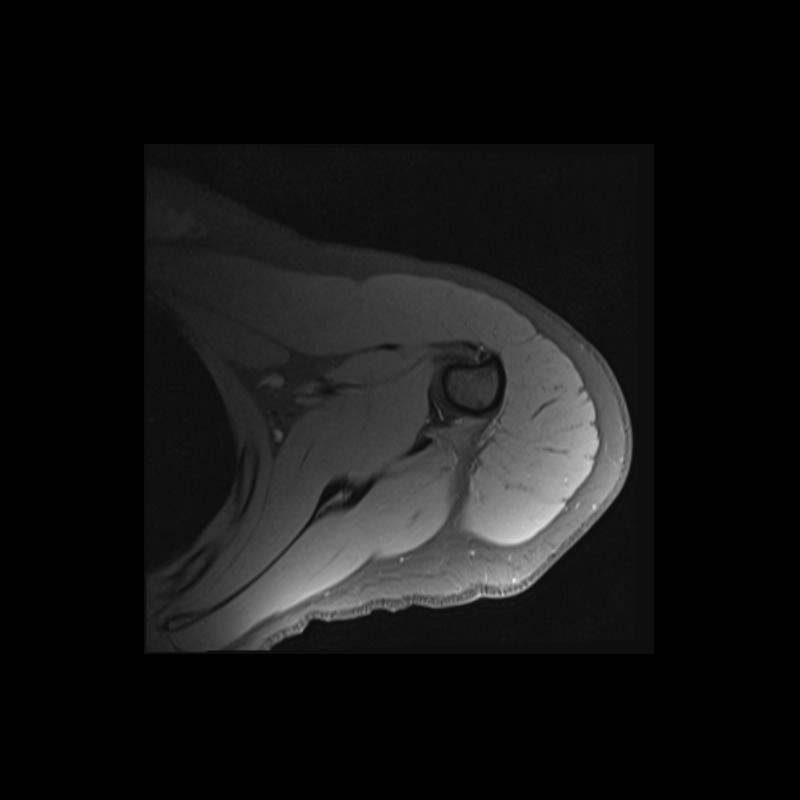

Shoulder MRI Anatomy